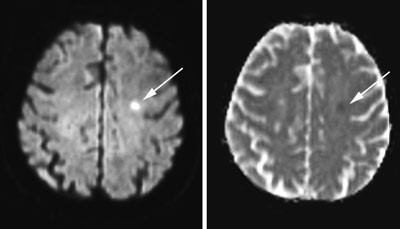

En stadig utvidet bruk av diffusjonsvektet MR har imidlertid vist at grensen mellom TIA og hjerneinfarkt patofysiologisk sett er flytende (6). Kidwell og medarbeidere fant, ved cerebral diffusjonsvektet MR undersøkelse utført i gjennomsnitt 17 timer etter debut av TIA, at 48 % av pasientene hadde en eller flere nye fokale lesjoner i hjernen (7). Det var høyest frekvens av lesjoner i de tilfellene der TIA hadde vart i over en time, og der pasienten hadde hatt pareser eller dysfasi. De aller fleste iskemiske lesjoner påvist ved diffusjonsvektet MR samsvarer med et infarktområde (8). Også etter invasive kardiovaskulære prosedyrer som hjertekateterisering finner man relativt ofte cerebrale lesjoner ved diffusjonsvektet MR, uansett om pasienten rapporterer TIA-symptomer eller ikke (9).

Diffusjonsvektet MR sannsynliggjør at de aller fleste TIA skyldes embolisme fordi de cerebrale lesjonene er små og velavgrensede (fig 1), og i mange tilfeller multifokale. MR kan også gi informasjon om etiologien ved det enkelte TIA. Dersom man ser akutte lesjoner i begge hemisfærer, eller i både det fremre (carotis) og det bakre (vertebrobasilaris) cerebrale kretsløp, er det meget sannsynlig at TIA skyldes kardioembolisme eller embolisme fra aortabuen. Emboluser fra et arteriosklerotisk plakk i a. carotis (arterie-til-arterie-embolisme) vil gi en eller flere lesjoner i samsidig hemisfære.